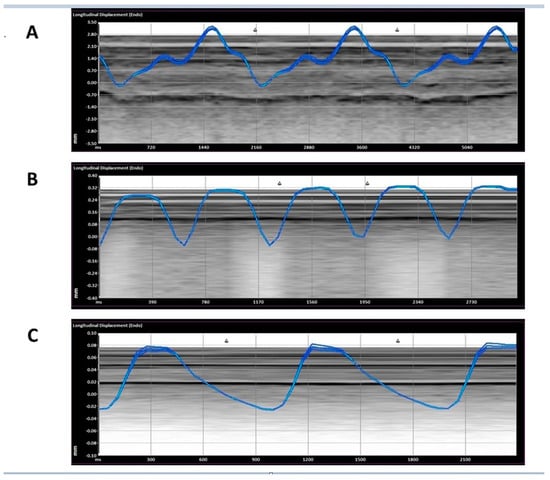

- The displacement of the pleura, when quantitated by a speckled tracking tool, varies significantly between ADHF patients, COVID-19 patients, and non-respiratory patients. ADHF pleura showed larger movements than in COVID-19, while the non-respiratory patients had a relatively small displacement (Figure 3, p < 0.01).

- The velocity of the pleural movement is significantly larger for the ADHF patients than for COVID-19 pneumonia patients; while the velocity for the non-respiratory patients was very small (Figure 4, p < 0.01).